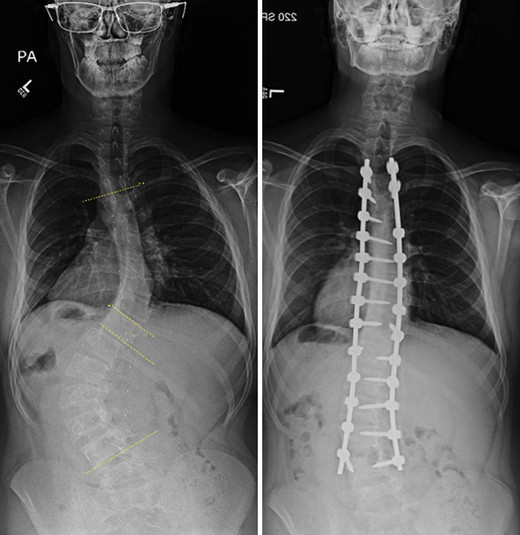

Подборка рентгеновских снимков, которые наглядно показывают, что от нас скрывает природа

Самые занимательные рентгеновские снимки, показывающие, что скрыто от глаз человека

Сегодня открытие немца используют во многих сферах жизни, начиная с медицины и заканчивая таможней. Собрали для вас самые занимательные рентгеновские снимки, показывающие, что скрыто от глаз человека.